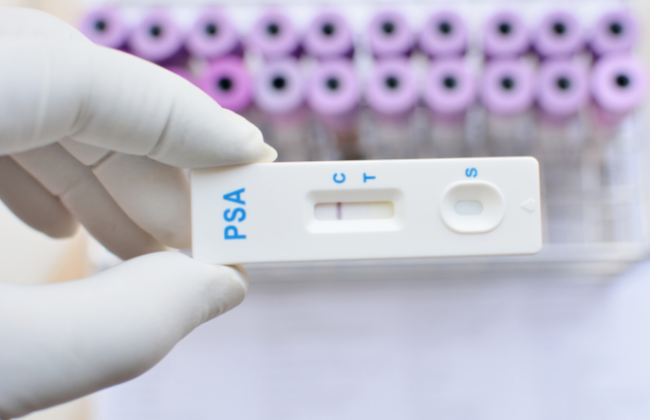

Jako że badanie NIFTY PRO jest badaniem bezinwazyjny, podczas którego pobierane jest jedynie 10ml krwi z żyły kobiety nie ma potrzeby specjalnego przygotowania się do takiego testu. Warto zwrócić uwagę na sterylność urządzeń, jakich używa się podczas pobrania krwi oraz poziom higieny miejsca, w jakim takie badanie się odbywa.